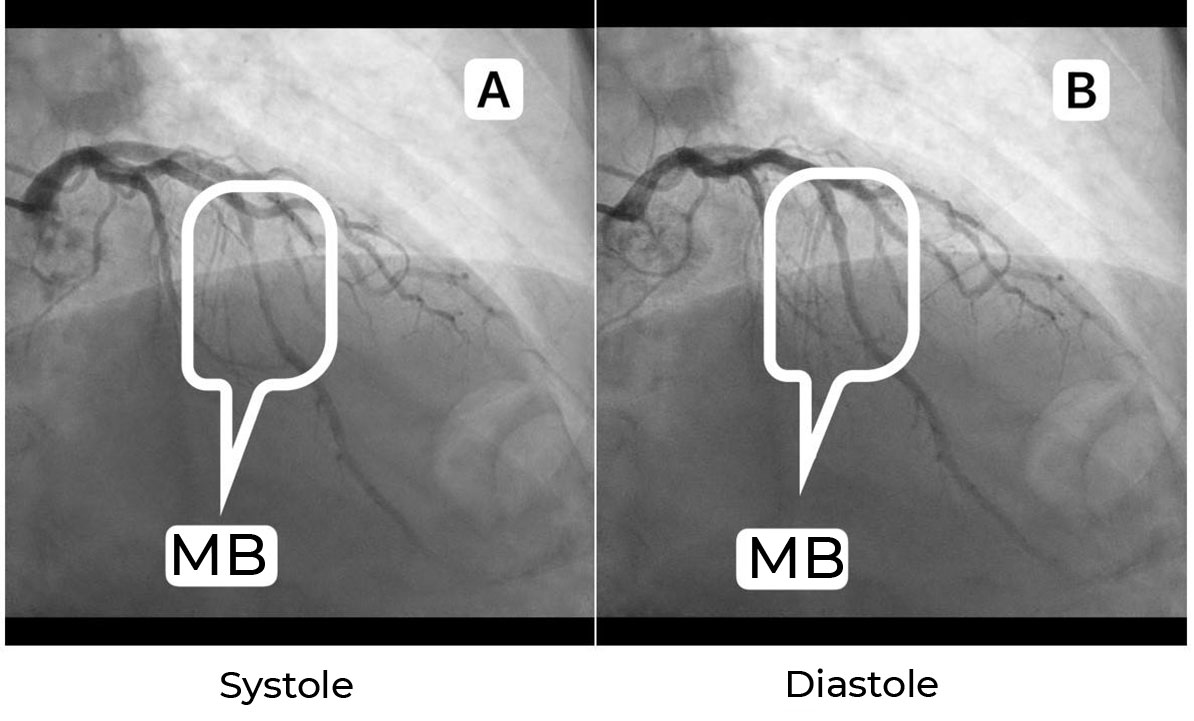

Многие исследователи приходят к заключению, что ММ в среднем встречаются в каждом третьем случае. Наименее чувствительным – от 0,5% [1] до 18% [2] – методом диагностики ММ является селективная коронарная ангиография (КАГ) (рисунок 1).

Рисунок 1. Типичные характеристики ММ при КАГ. На изображении (А) визуализируется фрагмент ММ, подвергающийся компрессии в систолу. В той же артерии во время диастолы (В) сегмент ММ не подвергается компрессии.

Figure 1. Typical characteristics of the myocardial bridge under angiography. Image (A) shows a MB fragment undergoing systole compression. In the same artery, the MB segment is not compressed during diastole (B).

Диагностическим симптомом ММ является «эффект доения» и/или феномен «шаг вниз – шаг вверх», вызванный сокращением мышцы в систолу. Стоит отметить, что КАГ коронарных артерий (КА) является «золотым стандартом», например, при диагностике гемодинамически значимых стенозов венечных артерий или шунтографии. Она имеет некоторые технические ограничения по сравнению с другими новыми методами визуализации, такими как внутрисосудистое ультразвуковое исследование и мультиспиральная компьютерная томографическая коронарная ангиография (КТ-КАГ). Проведение КТ-КАГ позволяет лучше визуализировать ММ – от 26,6% [3] до 73% [4] случаев. Компьютерная томография определяет ММ как фрагмент артерии, который частично или полностью окружен миокардом. Последние разработки, позволяющие выполнять функциональную оценку, дополнительно повышают диагностическую ценность КТ-КАГ для выявления гемодинамически значимых ММ (рисунок 2).